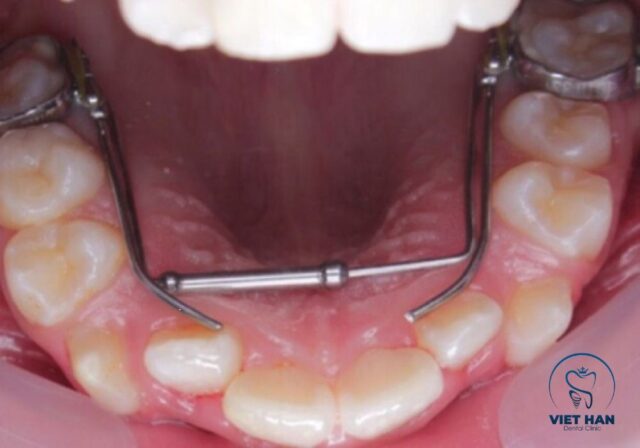

Nong hàm là kỹ thuật trong chỉnh nha sử dụng khí cụ chuyên dụng để mở rộng cung hàm, giúp tăng diện tích vòm miệng và tạo khoảng trống cho răng dịch chuyển.

Khí cụ nong hàm giúp mở rộng cung hàm, hỗ trợ niềng răng hiệu quả.

Phương pháp này thường áp dụng cho hàm trên và được thực hiện trước hoặc trong quá trình niềng răng. Khi cung hàm đủ rộng, các răng có thể sắp xếp đều mà không cần nhổ răng trong nhiều trường hợp. Nong hàm đóng vai trò quan trọng trong việc tối ưu hiệu quả chỉnh nha, giúp cải thiện khớp cắn và tăng tính thẩm mỹ tổng thể.